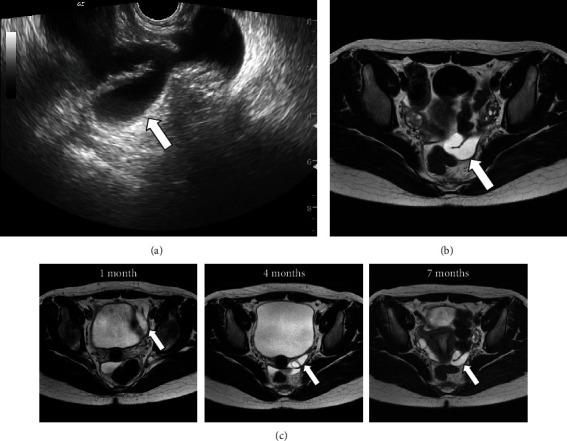

A 15-year-old female patient with no history of abdominal surgery or sexual intercourse presented with acute left lower abdominal pain and purpura. MRI revealed hydrosalpinx in the left adnexal region. Her abdominal pain had completely resolved at our examination; she was followed up as an outpatient. One month after the initial presentation, she experienced a large volume of watery discharge. Magnetic resonance imaging, which was performed every three months, showed a gradual decrease in the size of the hydrosalpinx; however, it persisted in the left adnexal region. She was counseled to receive laparoscopy to treat the hydrosalpinx, which was the most likely cause of the watery discharge. IFTT was detected during the laparoscopy, and left salpingectomy was performed for pathological evaluation of the persistent hydrosalpinx. Following laparoscopy, the patient's watery discharge was resolved. Pathological findings confirmed no signs of malignancy.

一名15岁女性患者,无腹部手术史及性交史,出现急性左下腹疼痛和紫癜。磁共振成像(MRI)显示左侧附件区输卵管积水。在我们检查时,她的腹痛已完全缓解;遂作为门诊患者进行随访。初次就诊后一个月,她出现大量水样分泌物。每三个月进行一次的磁共振成像显示输卵管积水的大小逐渐减小;然而,其仍存在于左侧附件区。建议她接受腹腔镜检查以治疗输卵管积水,这很可能是水样分泌物的病因。在腹腔镜检查期间发现了IFTT,并进行了左侧输卵管切除术以对持续存在的输卵管积水进行病理评估。腹腔镜检查后,患者的水样分泌物消失。病理结果证实无恶性迹象。